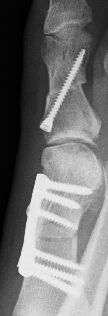

...Nasenscheidewand am 14.11.2013 und beide großen Zehen am 11.12.2013 - abwechlungsreich ist es aber.